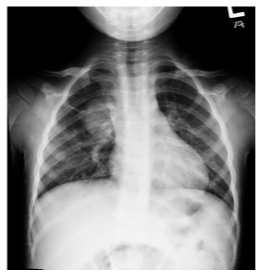

Leia o caso clínico a seguir.

Paciente de sete anos, do sexo masculino, apresenta tosse e febre há cinco dias. Ao exame físico, observa-se prostração e frequência respiratória de 48 IRPM. À ausculta, nota-se presença de estertores finos (crepitantes) em campo médio direito. A radiografia de tórax em PA é evidenciada a seguir.

Nesse caso, a etiologia é: